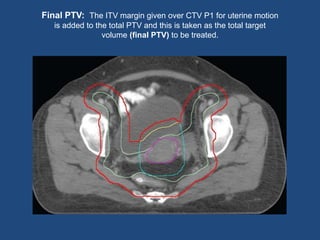

ITV Margin:The uterine motion is accounted for by giving an ITV margin

on the uterus….???

An asymmetrical margin with ITV expansion of 15 mm antero-posteriorly, 15mm

supero-inferiorly and 7 mm laterally, is taken from the uterus (CTV P1)

Final PTV: The ITV margin given over CTV P1 for uterine motion

is added to the total PTV and this is taken as the total target

volume (final PTV) to be treated.

Total CTV: CTVN and the CTV primary (CTVP1 & CTVP2) are combined and named as total CTV PTV: 10 mm over total CTV ITV Margin:The uterine motion is accounted for by giving an ITV margin on the uterus….??? An asymmetrical margin with ITV expansion of 15 mm antero-posteriorly, 15mm supero-inferiorly and 7 mm laterally, is taken from the uterus (CTV P1)

• 15.

Final PTV: TheITV margin given over CTV P1 for uterine motion is added to the total PTV and this is taken as the total target volume (final PTV) to be treated.